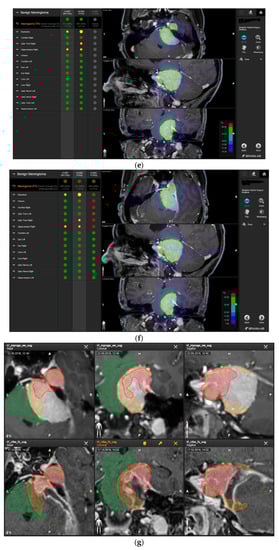

A 58-year-old female presented with progressive headache, difficulty swallowing, diplopia, hearing loss, and reduced face sensitivity on the right side (Figure 4). Elective craniotomy and AHSA-assisted tumor resection were performed. The patient underwent hypofractionated radiosurgery (5 × 5 Gy) of the residual meningioma one year after tumor resection.

Figure 4.

Second representative case of AHSA-supported tumor resection. (a) MRI imaging of petroclival meningioma (axial, coronal, sagittal). (b) Depiction of preoperative tumor volume (orange) and planned residual tumor volume (red). (c) AHSA summary table showing the stereotactic radiation constraints for the preoperatively planned residual tumor volume. With this plan, conventional fractionation and hypofractionation were feasible with effective tumor coverage.

—brainstem: mean dose is safe, while the max. dose is marginally safe;

—right optic tract: mean dose unsafe, max. dose is marginally safe;

—right hippocampus: marginally safe, and mean dose unsafe, max. dose is marginally safe. (d) First intraoperative structure update (ISU) with a residual tumor volume of 82% with the calculated dose constraints for conventional and hypofractionated radiotherapy. Single dose stereotactic radiosurgery was not feasible with this degree of remaining tumor. At this point, the dose constraints for conventional radiotherapy were:

—brainstem: mean dose is safe, max. dose is marginally safe;

—right hippocampus: mean dose unsafe, max. dose is marginally safe. Hypofractionated radiotherapy:

—brainstem: marginally safe;

—right cochlea: mean dose unsafe, max. dose safe;

—right hippocampus: mean dose unsafe, max. dose is marginally safe. (e) Second intraoperative ISU with residual tumor volume of 74% and calculated dose constraints for hypofractionated radiotherapy. Single dose stereotactic radiosurgery was still not considered feasible with this residual tumor volume. The dose constraints for organs at risk for conventional and hypofractionated radiotherapy were unchanged compared to the first ISU. (f) Third intraoperative ISU with residual tumor volume of 47% and calculated dose constraints for conventional, hypofractionated radiotherapy, and radiosurgery. The current dose constraints for organs at risk were the following for conventional radiation:

—right hippocampus: mean dose unsafe, max. dose is marginally safe. Hypofractionated radiation, which was unchanged for the first and second ISU:

—right hippocampus: mean dose unsafe, max. dose is marginally safe. For single fraction radiosurgery, the OAR dose constraints were available but considered to be unsafe.

—brainstem: mean dose unsafe, max. dose safe;

—chiasma: unsafe;

—right cochlea: unsafe;

—left optic tract: mean dose unsafe, max. dose safe;

—right optic tract: unsafe;

—right hippocampus: unsafe. (g) Overlay of preoperatively estimated and intraoperative effective residual tumor volume in AHSA. (h) Final intraoperative dose constraints after last ISU and data fusion with intraoperative CT. The dose constraints for OARs appeared to improve and were as follows for conventional and hypofractionated radiotherapy:

—brainstem: mean dose is safe, max. dose is marginally safe.

—brainstem: mean dose safe, max. dose unsafe;

—chiasm: mean dose unsafe, max. dose safe;

—right optic tract: mean dose unsafe, max. dose safe. (i) Comparison of pre- and 3 months postoperative MRI for stereotactic radiation planning. The residual tumor was finally treated with hypofractionated radiotherapy (5 × 5 Gy).